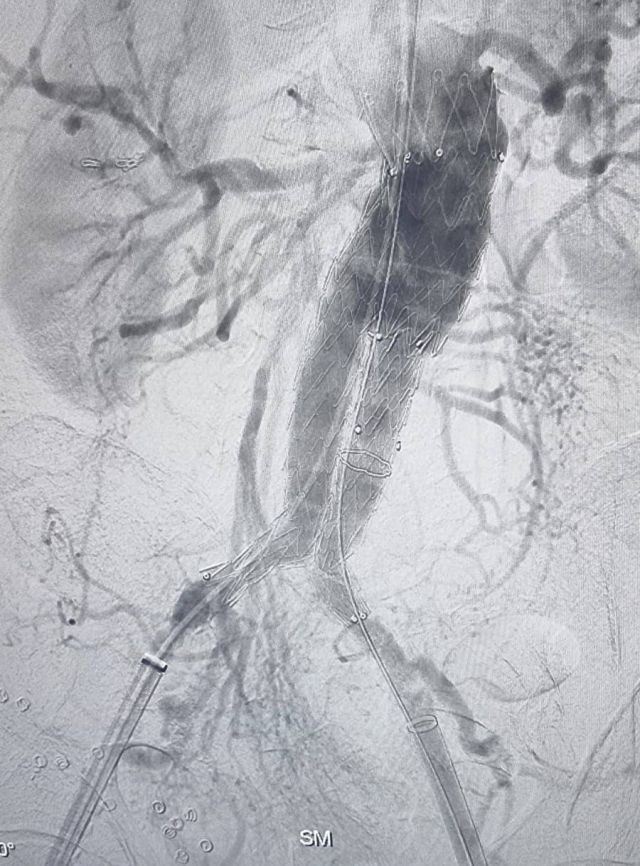

ليتضح بعد إجراء الفحوص السريرية والمخبرية والإشعاعية أن المريض لديه تمدد كبير في الشريان الأورطي بالبطن يتجاوز طوله الـ ٧ سم أدى إلى الضغط على الفقرات القطنية مسبباً آلاماً حادة.

وعلى الفور، قرر الفريق الطبي إجراء تدخل جراحي لتركيب دعامة من طريق قسطرة الأوعية التداخلية تحت تأثير المخدر الكلي. وقد جرى التدخل من دون أي مضاعفات ليتم نقل المريض إلى العناية المركزة للمتابعة الدقيقة حتى خروجه من المستشفى.

وأكد الفريق الطبّي أن هذا النوع من العمليات بالغ الخطورة، لأن الشريان الأورطي هو الشريان الرئيسي في الجسم، وقد يسبّب انفجاره نزيفاً داخلياً يؤدي إلى الوفاة.